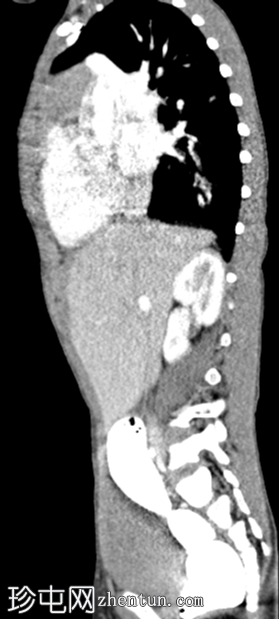

冠状面

非造影

左侧膈疝通过位于左膈中部的一个缺损形成,伴有纵隔向右侧移位,下方左塌陷。

脾脏、大肠和小肠均有疝气,同时伴有肠系膜上血管疝气。

胃位于下部,靠近主动脉分叉处。

在降结肠和直肠中可见先前荧光透视检查的残留造影剂。